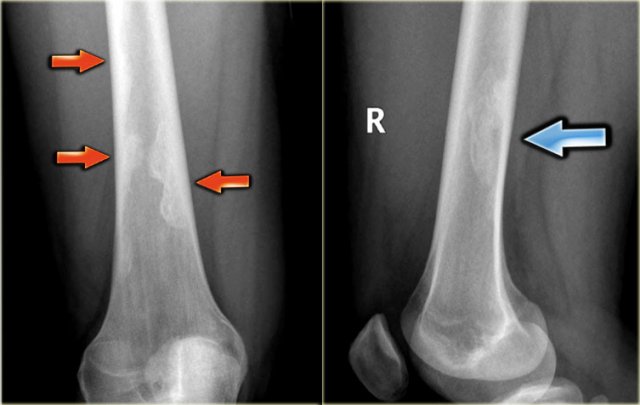

Here a NHL presenting as a non-specific ill-defined mixed osteolytic-sclerotic lesion in the proximal tibia.

Here a bone lesion in a patient with known NHL.

The imaging findings are non specific.